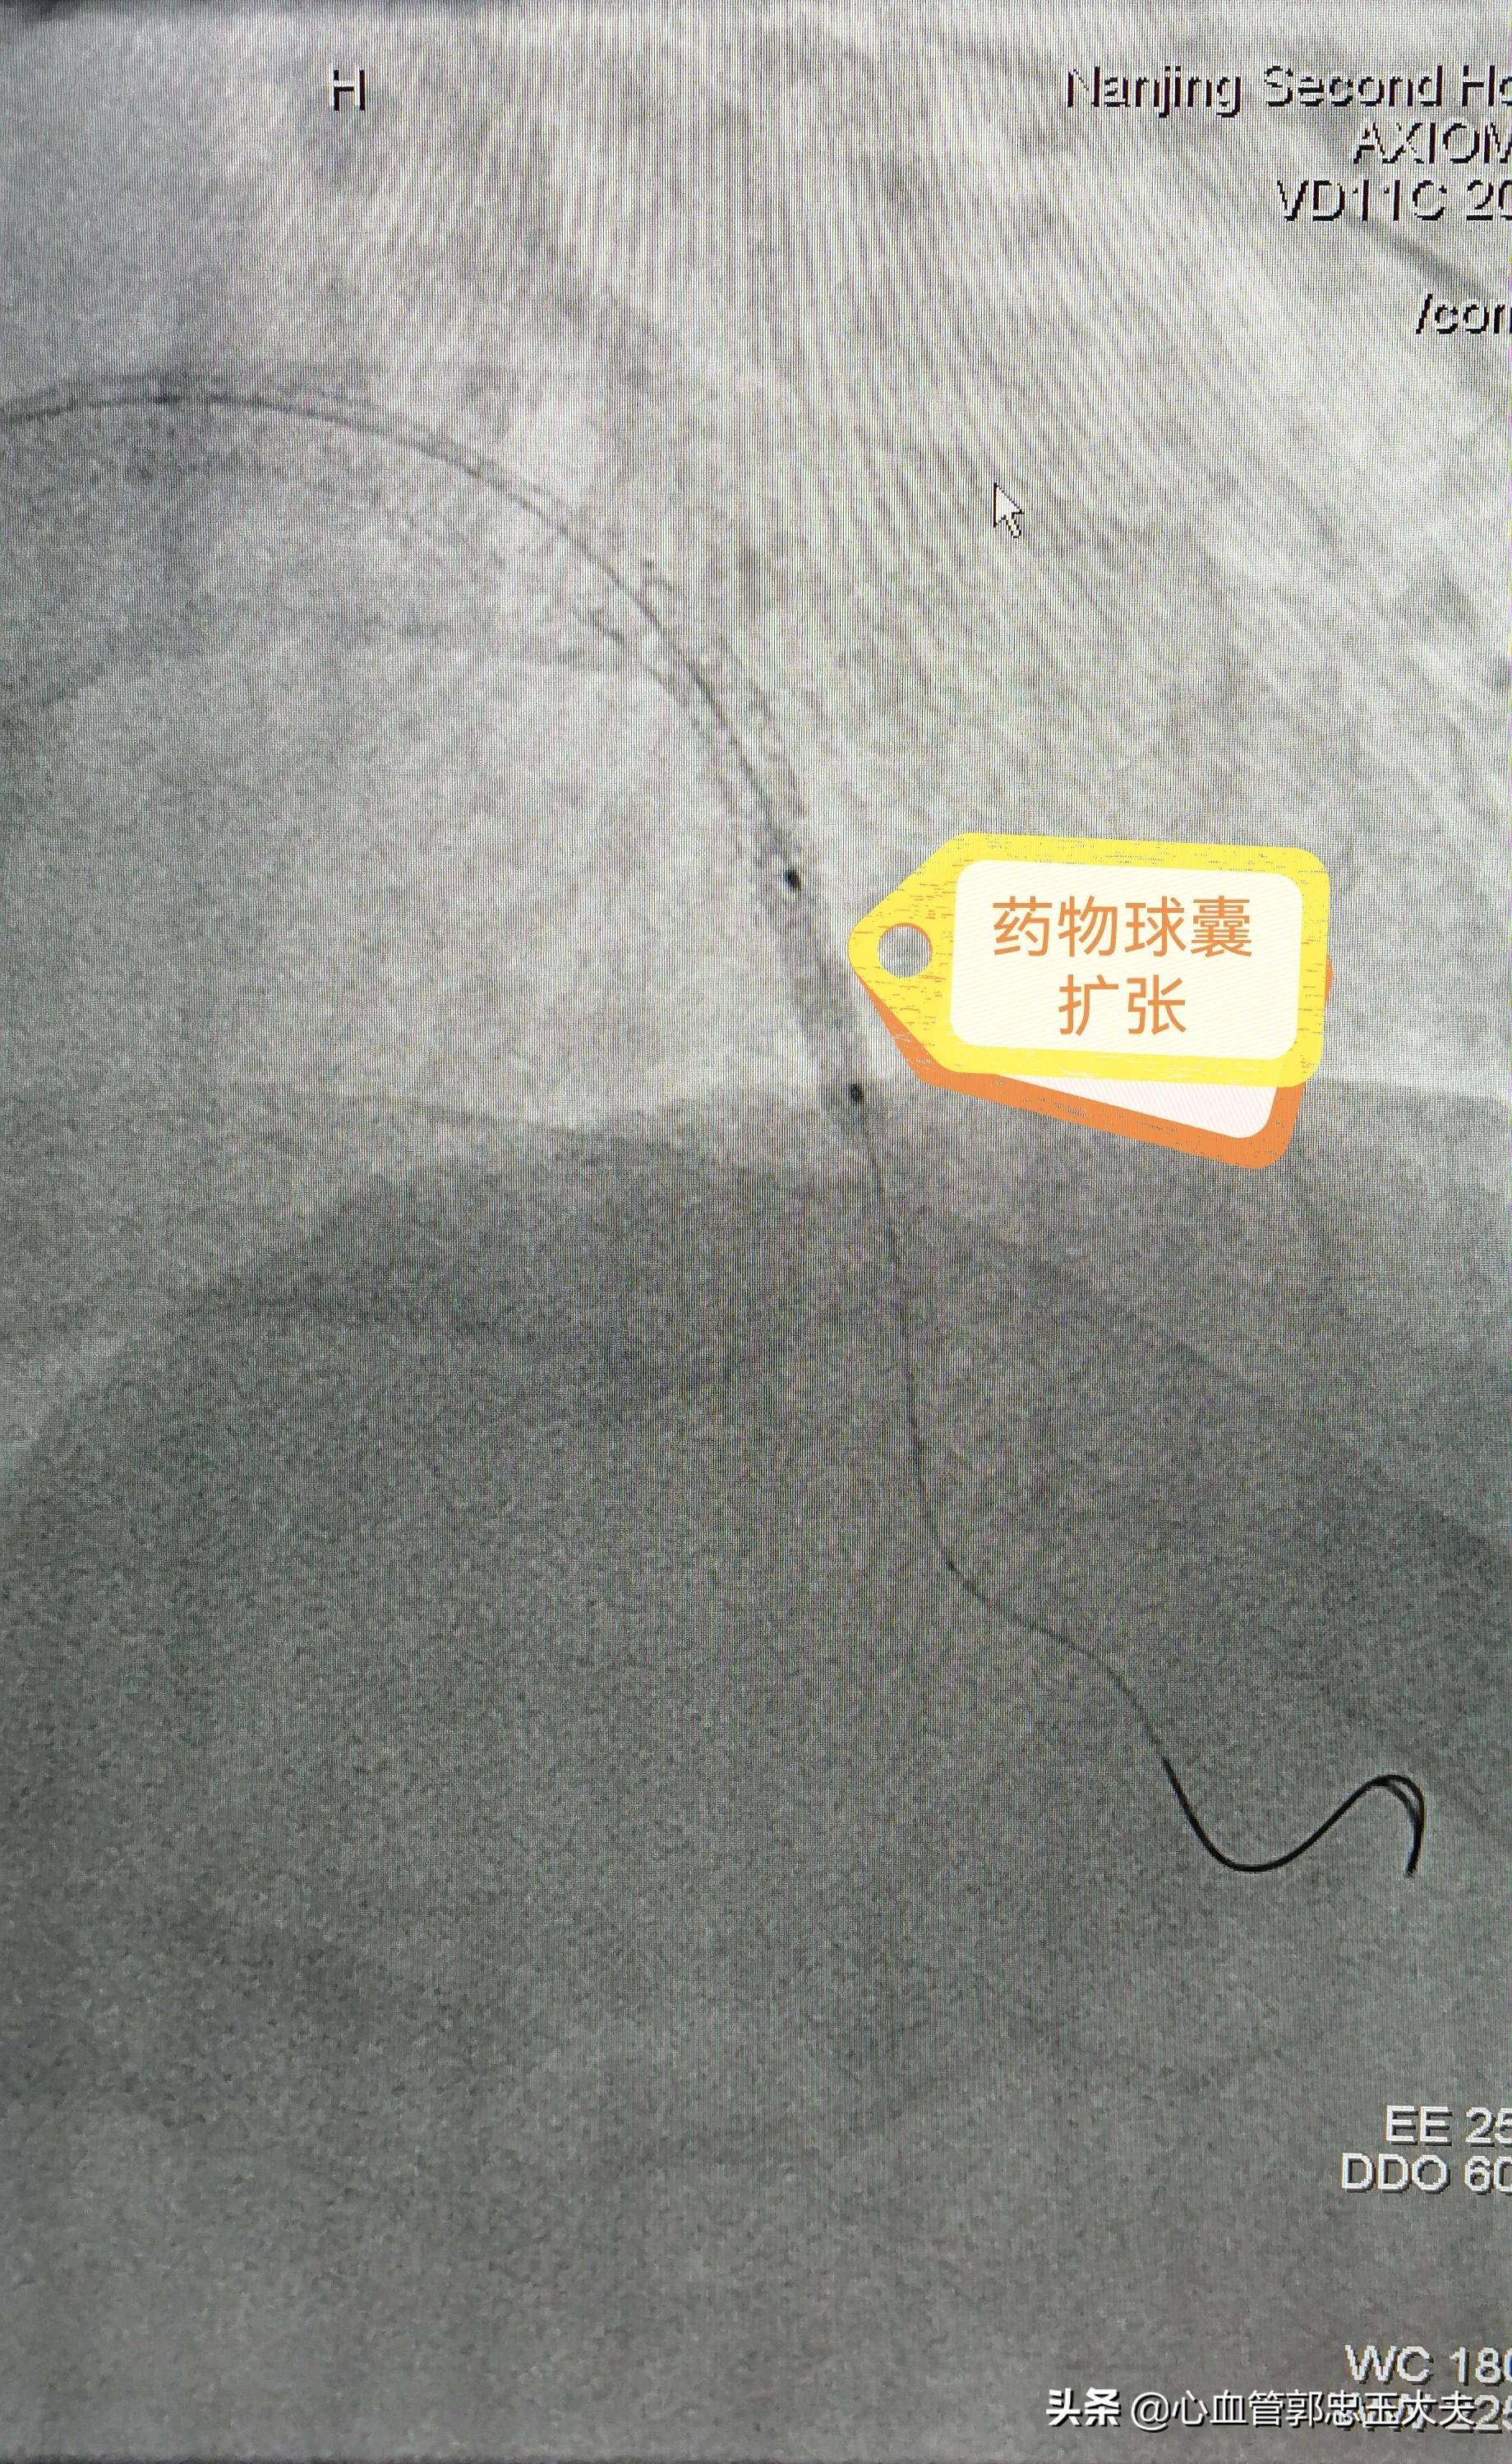

由于患者已经做过一次支架,去年5月份复查过一次造影血管是“好的”,对再次造影很*制抵**,考虑到 典型的劳力性心绞痛症状及心电图缺血改变 ,还是 决定冠脉造影检查 。经过与本人及家属反复沟通,终于同意造影。术中造影示:前降支近段到中远段可见支架影,支架内血流顺畅, 支架内远端及边缘血管80%狭窄 ,按照 支架内再狭窄定义:支架内及边缘5mm内血管再次50%以上狭窄 。考虑 支架内再狭窄 。患者及家属拒绝再次植入支架,故选用药物球囊扩张,术后狭窄消失,未见夹层形成。手术圆满结束。

药物球囊扩张